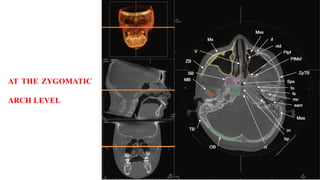

AT THE ZYGOMATIC

ARCH LEVEL